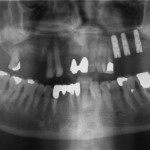

Efficacia a lungo termine degli impianti corti

Con il termine di impianti corti si descrivono tutti gli impianti dentali con forma e materiali convenzionali, ma di lunghezza inferiore ai 10 mm. Gli...